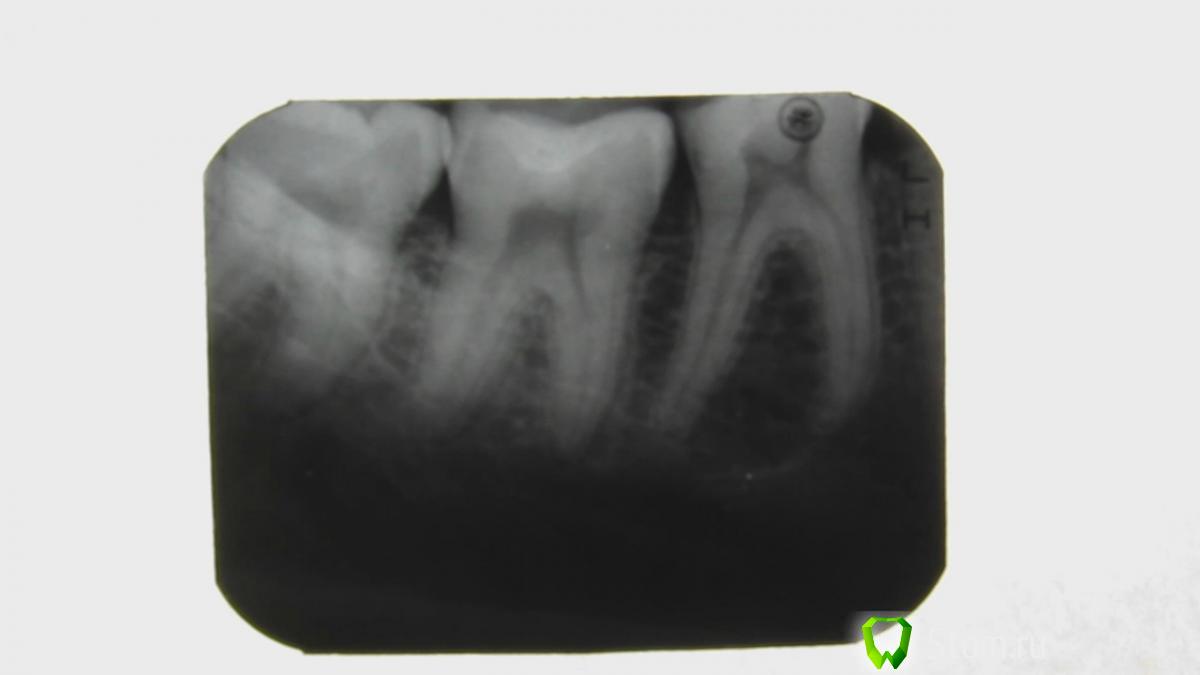

F.e.r.u.m Опубликовано 18 февраля, 2012 Автор Поделиться Опубликовано 18 февраля, 2012 Спасибо всем за ответы.К вечеру следующего дня, после старт-поста ноющая боль уменьшилась, а наутро и вовсе ушла. Однако боль при накусывании осталась такая же сильная, только утихает быстрее. Выкладываю рентген снимок Ссылка на комментарий

DokDent Опубликовано 18 февраля, 2012 Поделиться Опубликовано 18 февраля, 2012 Спасибо всем за ответы.К вечеру следующего дня, после старт-поста ноющая боль уменьшилась, а наутро и вовсе ушла. Однако боль при накусывании осталась такая же сильная, только утихает быстрее. Выкладываю рентген снимок По снимку больше болит 6-ка(самопроизвольные,длительные и стреляющие боли при накусывании-пломба находится близко от нерва). Ссылка на комментарий

Salma Опубликовано 18 февраля, 2012 Поделиться Опубликовано 18 февраля, 2012 судя по этому снимку пломба очень оченьблизко к нерву 6 зуба, думаю причина в нем Ссылка на комментарий